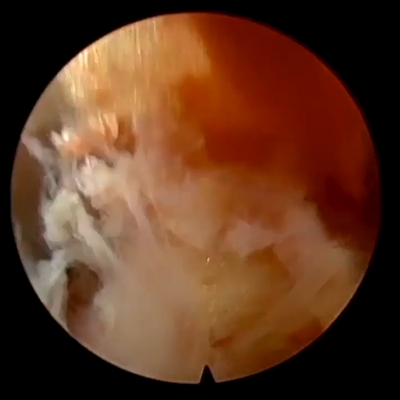

Click on an image below to view more info.